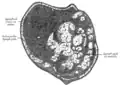

Section of small lymph node of rabbit. X 100.